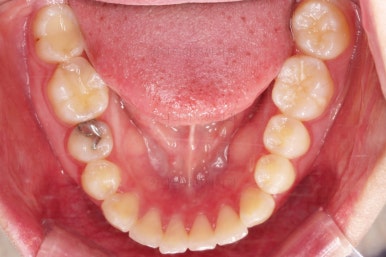

치아 갯수 및 사이즈 문제로 위아래의 정중선은 100% 일치시키긴 힘들지만 가능한 선에서 최대한 맞추었고요.

윗니가 1개 없는 상태에서의 교합도 잘 맞추고 마무리를 했습니다.

다시 틈새가 벌어지지 말라고 유지철사를 붙여주었고요.

전후 비교해 볼게요.

임플란트 하러 오신 분을 임플란트 없이 마무리 했고요.

젊으신 나이에 임플란트를 하기 보다는 약간의 시간을 더 투자해서 이렇게 마무리를 하는게 여러모로 합리적인 치료였습니다.